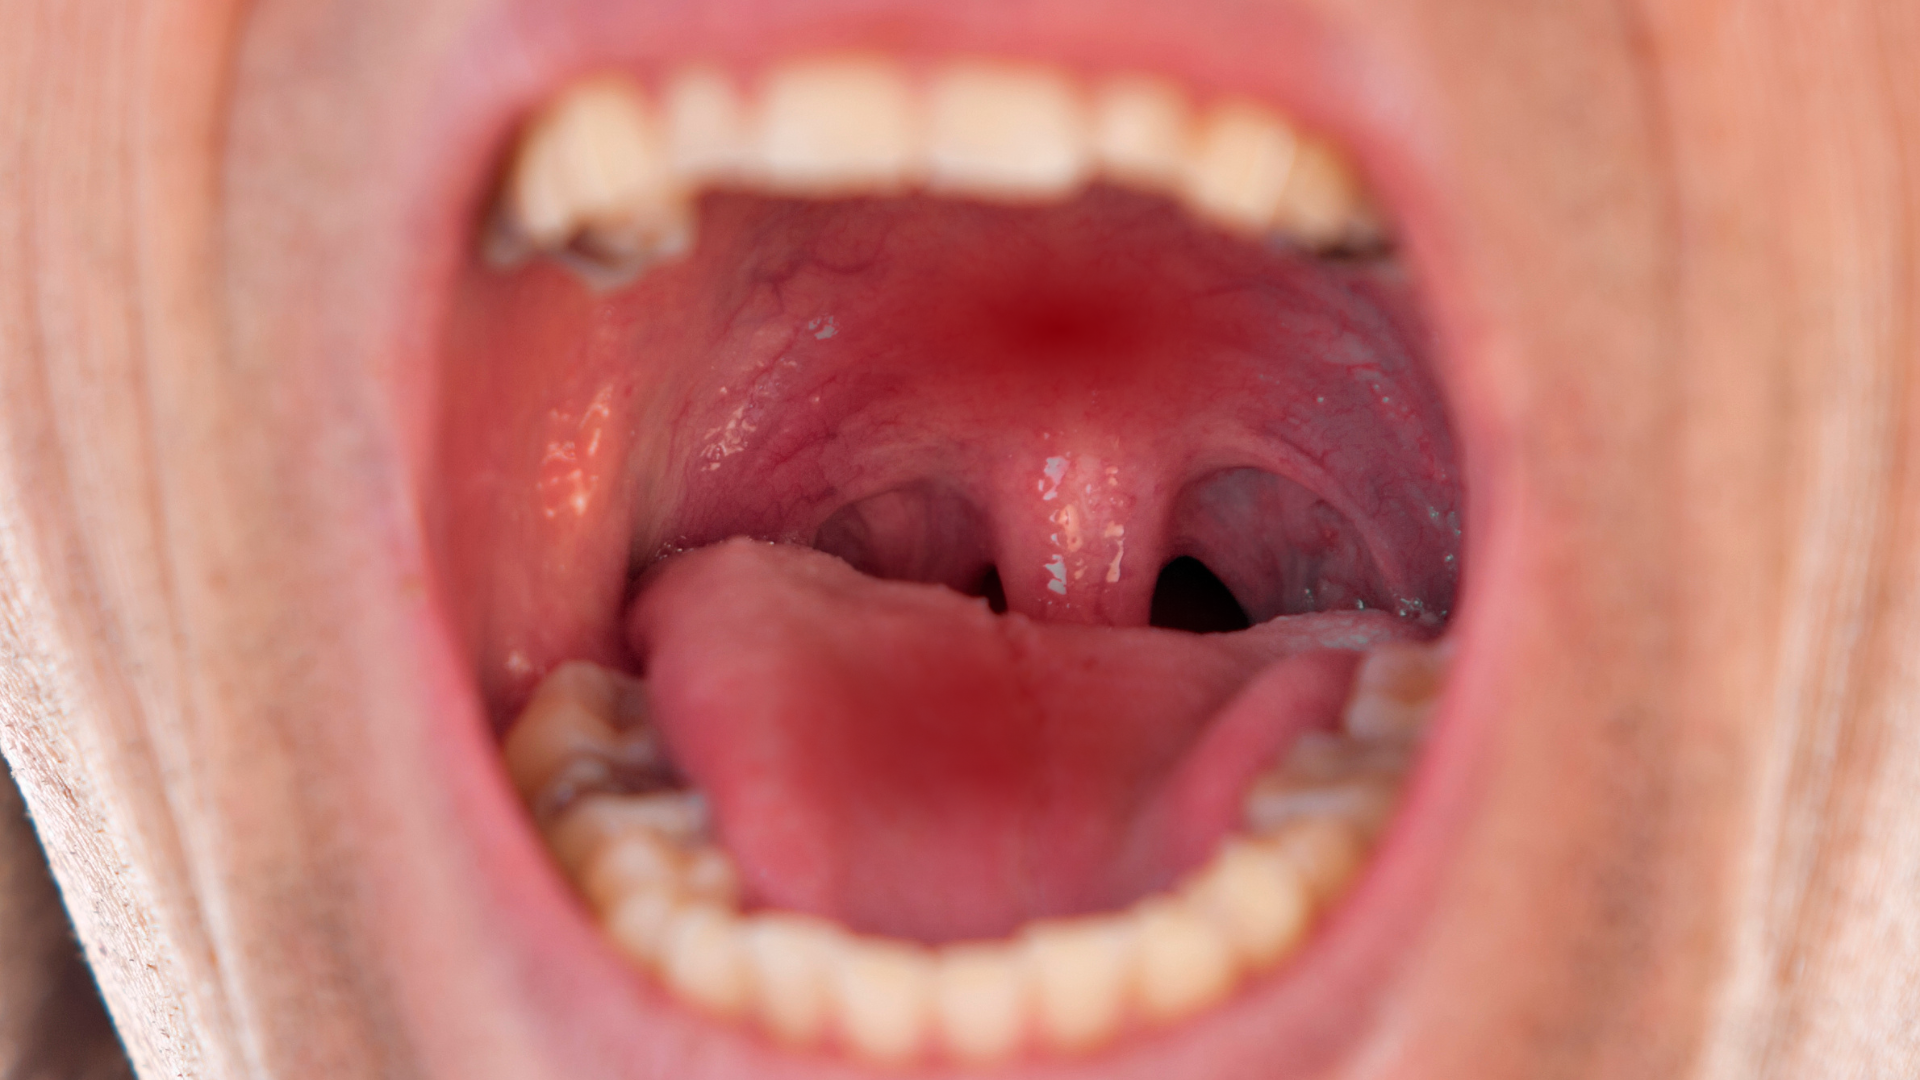

Hình ảnh qua nội soi tai mũi họng

Khi nội soi, bác sĩ có thể nhận thấy một số đặc điểm sau:

- Niêm mạc vòm họng xuất hiện vùng dày lên nhẹ, màu sắc thay đổi so với xung quanh.

- Có thể thấy mảng sùi nhỏ, phẳng hoặc hơi gồ, bề mặt không đều.

- Một số trường hợp xuất hiện vết trợt, loét nông, dễ chảy máu khi chạm vào.

Những hình ảnh này khác với viêm họng thông thường ở chỗ tổn thương thường khu trú một bên, không đối xứng và không cải thiện sau điều trị kháng viêm thông thường.